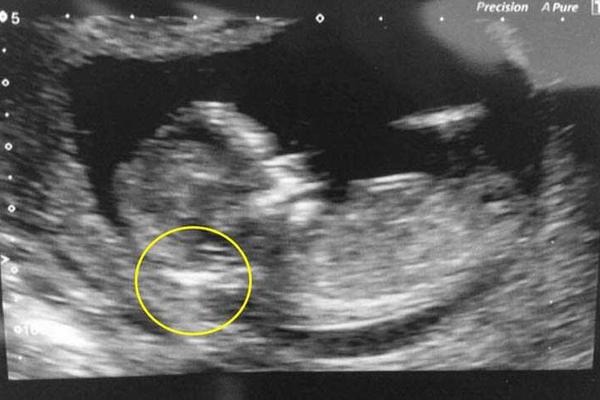

Kad je ginekolog video OVAJ DETALJ na ultrazvuku, rekao mi je da ŠTO PRE ABORTIRAM: Rodila sam i ostala u ŠOKU